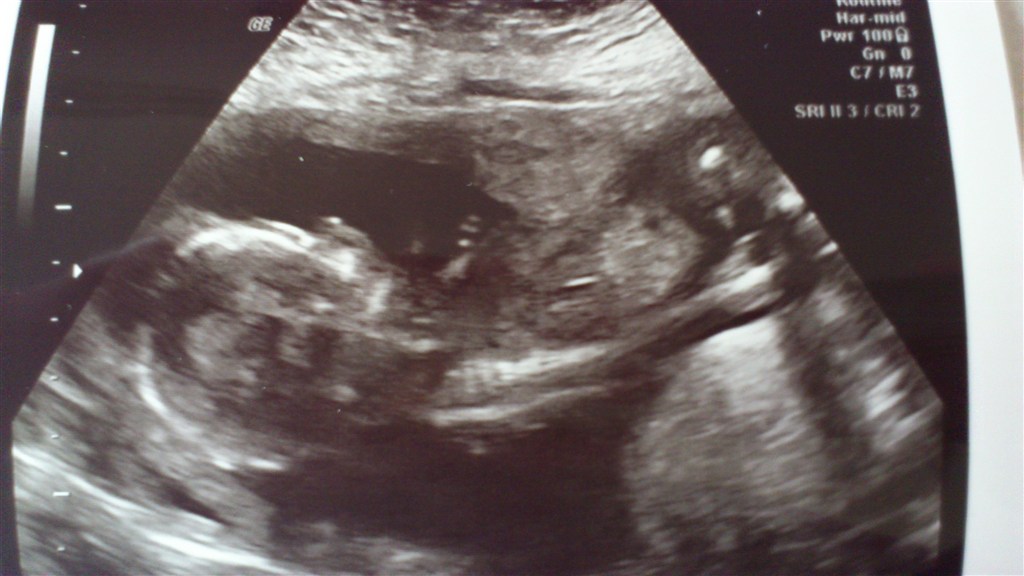

I får lige et par billeder af ham!

Vedhæftede fotos (klik for at se i fuld størrelse)